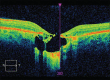

Macular coloboma is a congenital defect of the retina and choroid in the macular region. It may appear due to an intrauterine inflammation or a developmental abnormality. Familial hypomagnesemia with hypercalciuria and nephrocalcinosis (FHHNC) is a result of malformation of the renal tubule. Its combination with ocular manifestations may be genetic, specifically in case of claudin-19 (CLDN-19) gene mutations. The combination of FHHNC and ocular manifestations is not always present in these patients. Optical coherence tomography (OCT) helps us diagnose this condition by allowing us to evaluate and confirm the absence of retina layers without histological examination. Although genetic testing is necessary to diagnose mutational alterations of the CLDN-19 gene, in our case, it was not necessary to diagnose the FHHNC patient with macular coloboma, since the diagnosis of ocular damage had been already accurately established by the OCT.